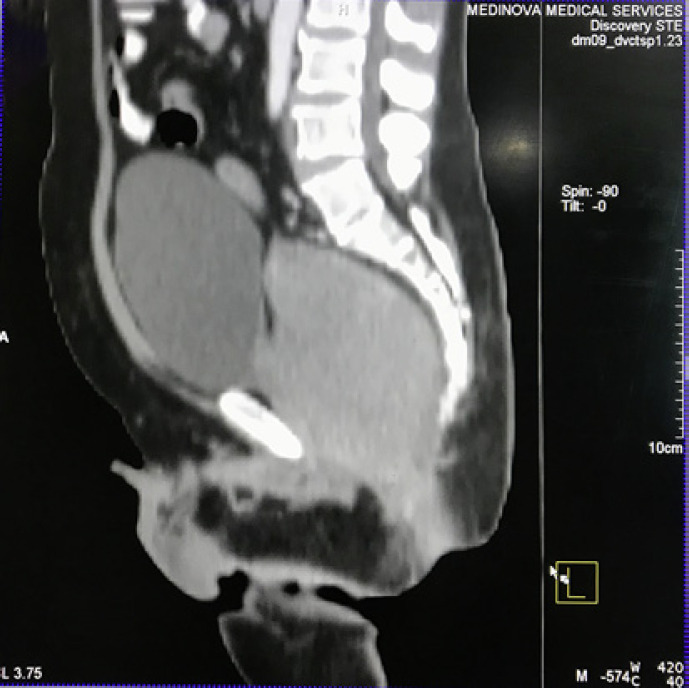

Primary Ovarian Non-Hodgkin’s Lymphoma with Late Diagnosis Due to Unusual Presentation - A Case Report

Involvement of NHL in ovary is seen in disseminated Lymphoma but primary ovarian lymphoma still not commonly seen. We presented the case where the patient had suffered for unexplained fever …

Treated with R-CHOP protocol for 6 cycles as IHC expressed CD20 positive. Post chemotherapy follow up PET scan showed complete response of treatment, though in …